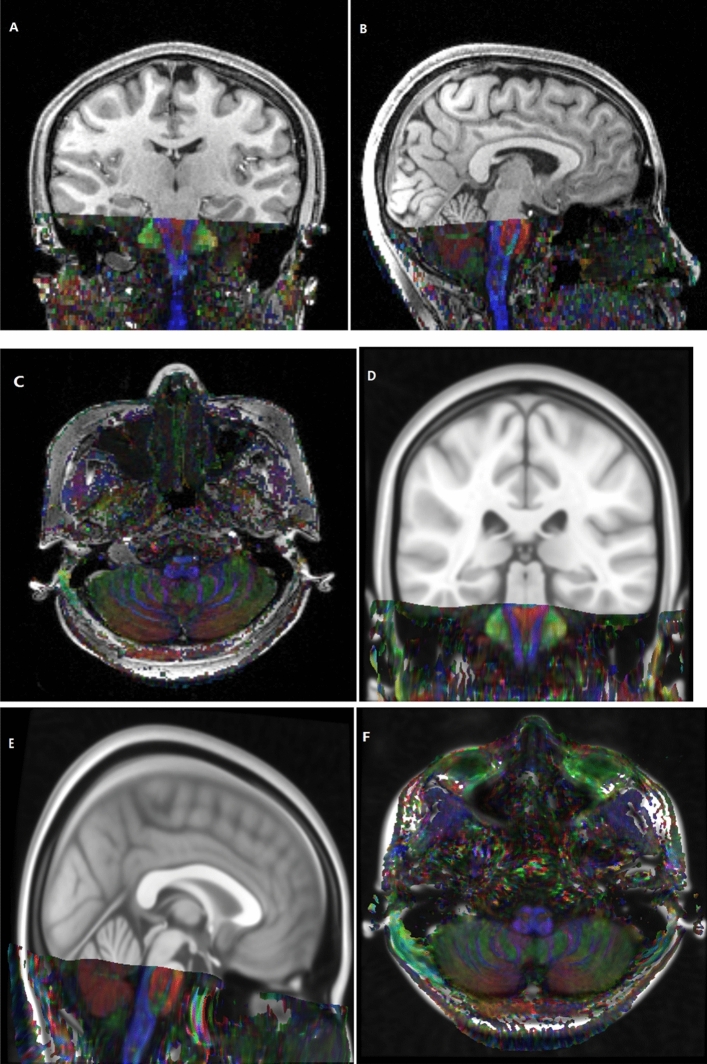

Figure 1.

A patient resource FA map with a voxel size of 1.2 mm × 1.2 mm × 3.0 mm was consistent in the common space of MNI152_T1_0.4 mm template with a voxel size of 0.4 mm3 by nonlinear registration.

In this study, the raw RESOLVE data were resampled to 0.4 mm3 voxel size by performing affine transformation and nonlinear registration in the common MNI152_T1_0.4 mm space (Fig. 1). The resampled RESOLVE data were used to track the intratemporal facial nerve fibers of each subject in the 0.4 mm3 group-level common space, and the MPMs of the different group were obtained (Fig. 4). To observe the microscopic differences of intratemporal facial nerve fibers, the DTI indexes based on the different MPMs nerve were extracted.